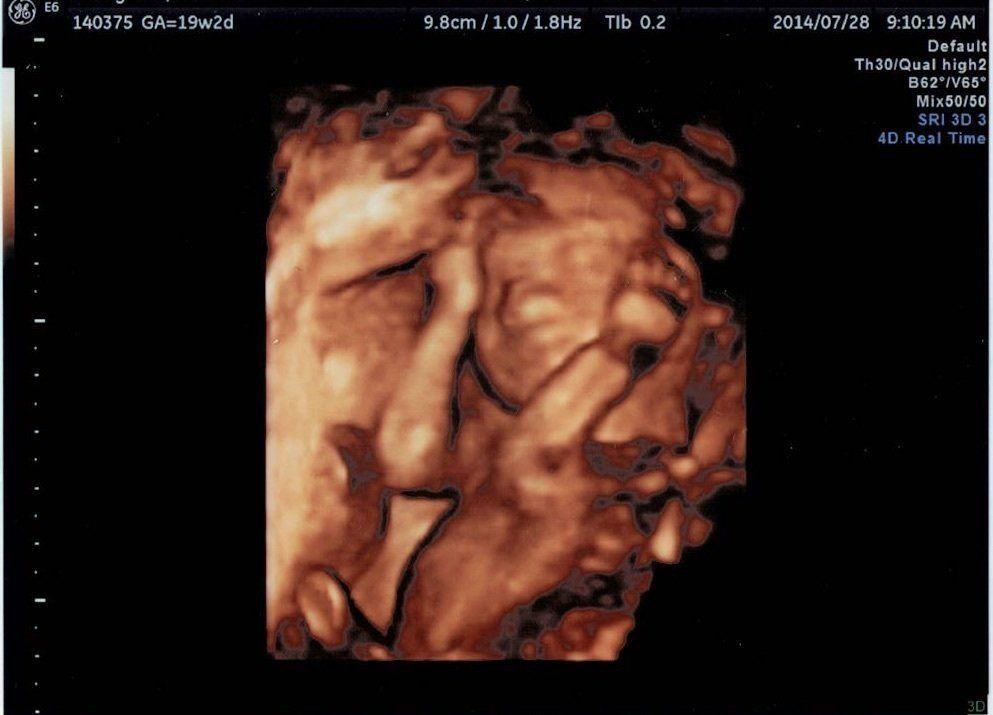

妊娠19週目エコー写真

親戚の結婚式へ出席するなど、この時期は安定した状態が続きました。今回は4Dエコーでした。これは一部を切り取った写真なのですが、実際は、赤ちゃんがリアルタイムに動いているところを、立体的な画像で見ることができます。最初は手で顔を隠していたわが子。親孝行なことに、4Dで様子を見ている最中に腕を動かして顔を見せてくれました。気になる性別は、股をがっちり閉じていて分かりませんでした。顔もお尻も隠して「恥じらいがある」と先生に褒めて(?)頂きました。